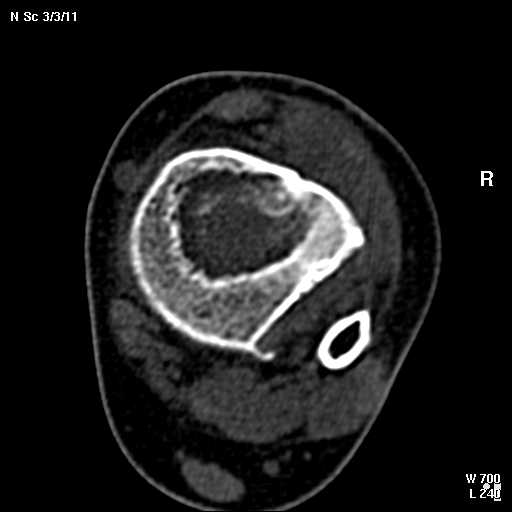

КТ изображения передаю на мой взгляд самые демонстративные. Их любезно записал коллега,

проводивший исследование в другом городе.

Прошу прощения за немного некоректную отправку КТ-снимков но по другому не получается :)

4